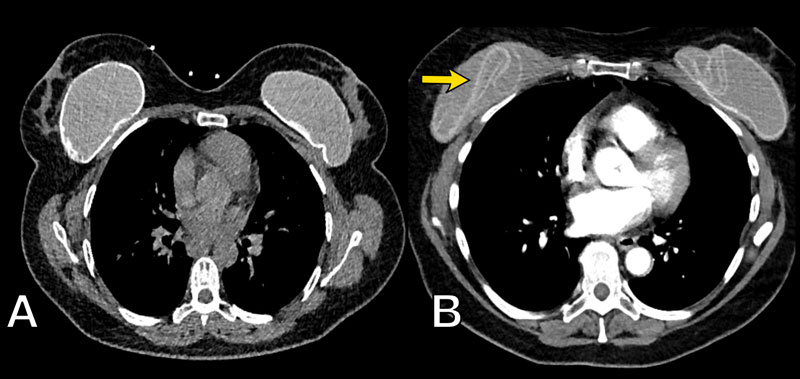

Breast implant ruptured